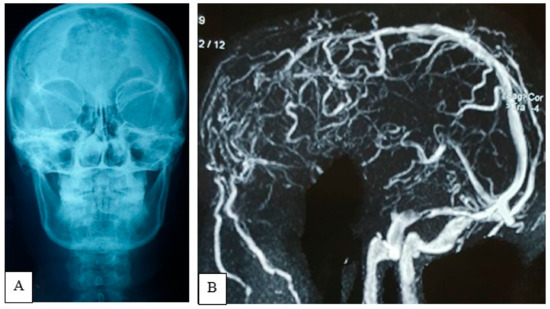

2.4.3. Preoperative Imaging

4.5. Neuroimaging Features and Differential Diagnosis